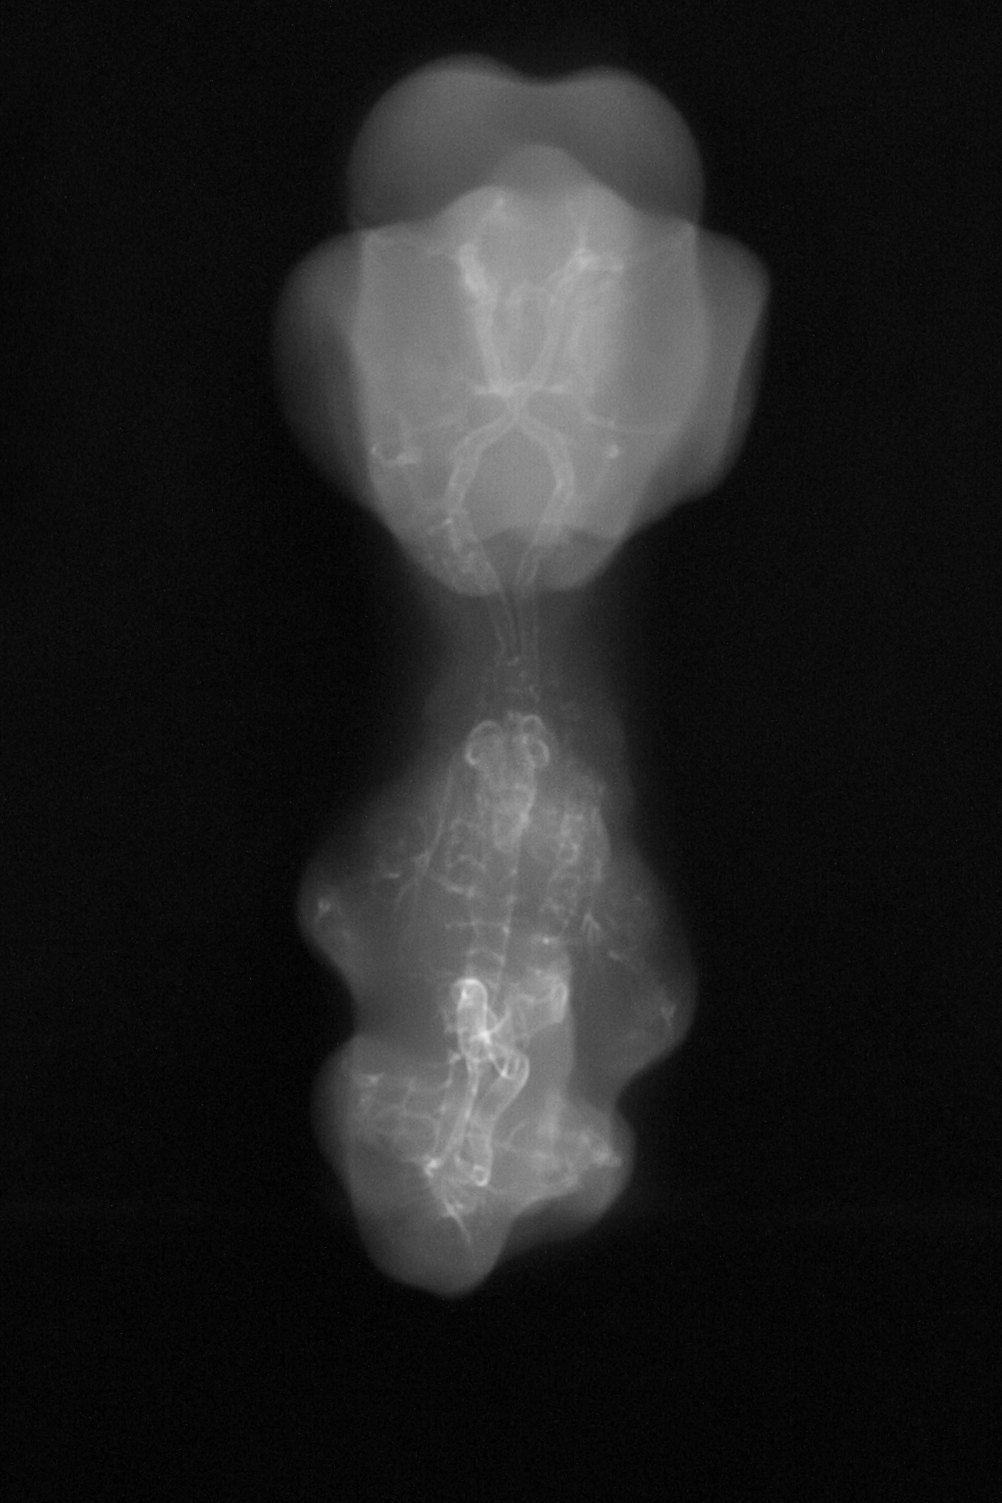

Chick Embryo Microangiography

Hamburger-Hamilton (HH) Stage 29 (approx. 6 - 6.5 days)

X-Ray Micrographs